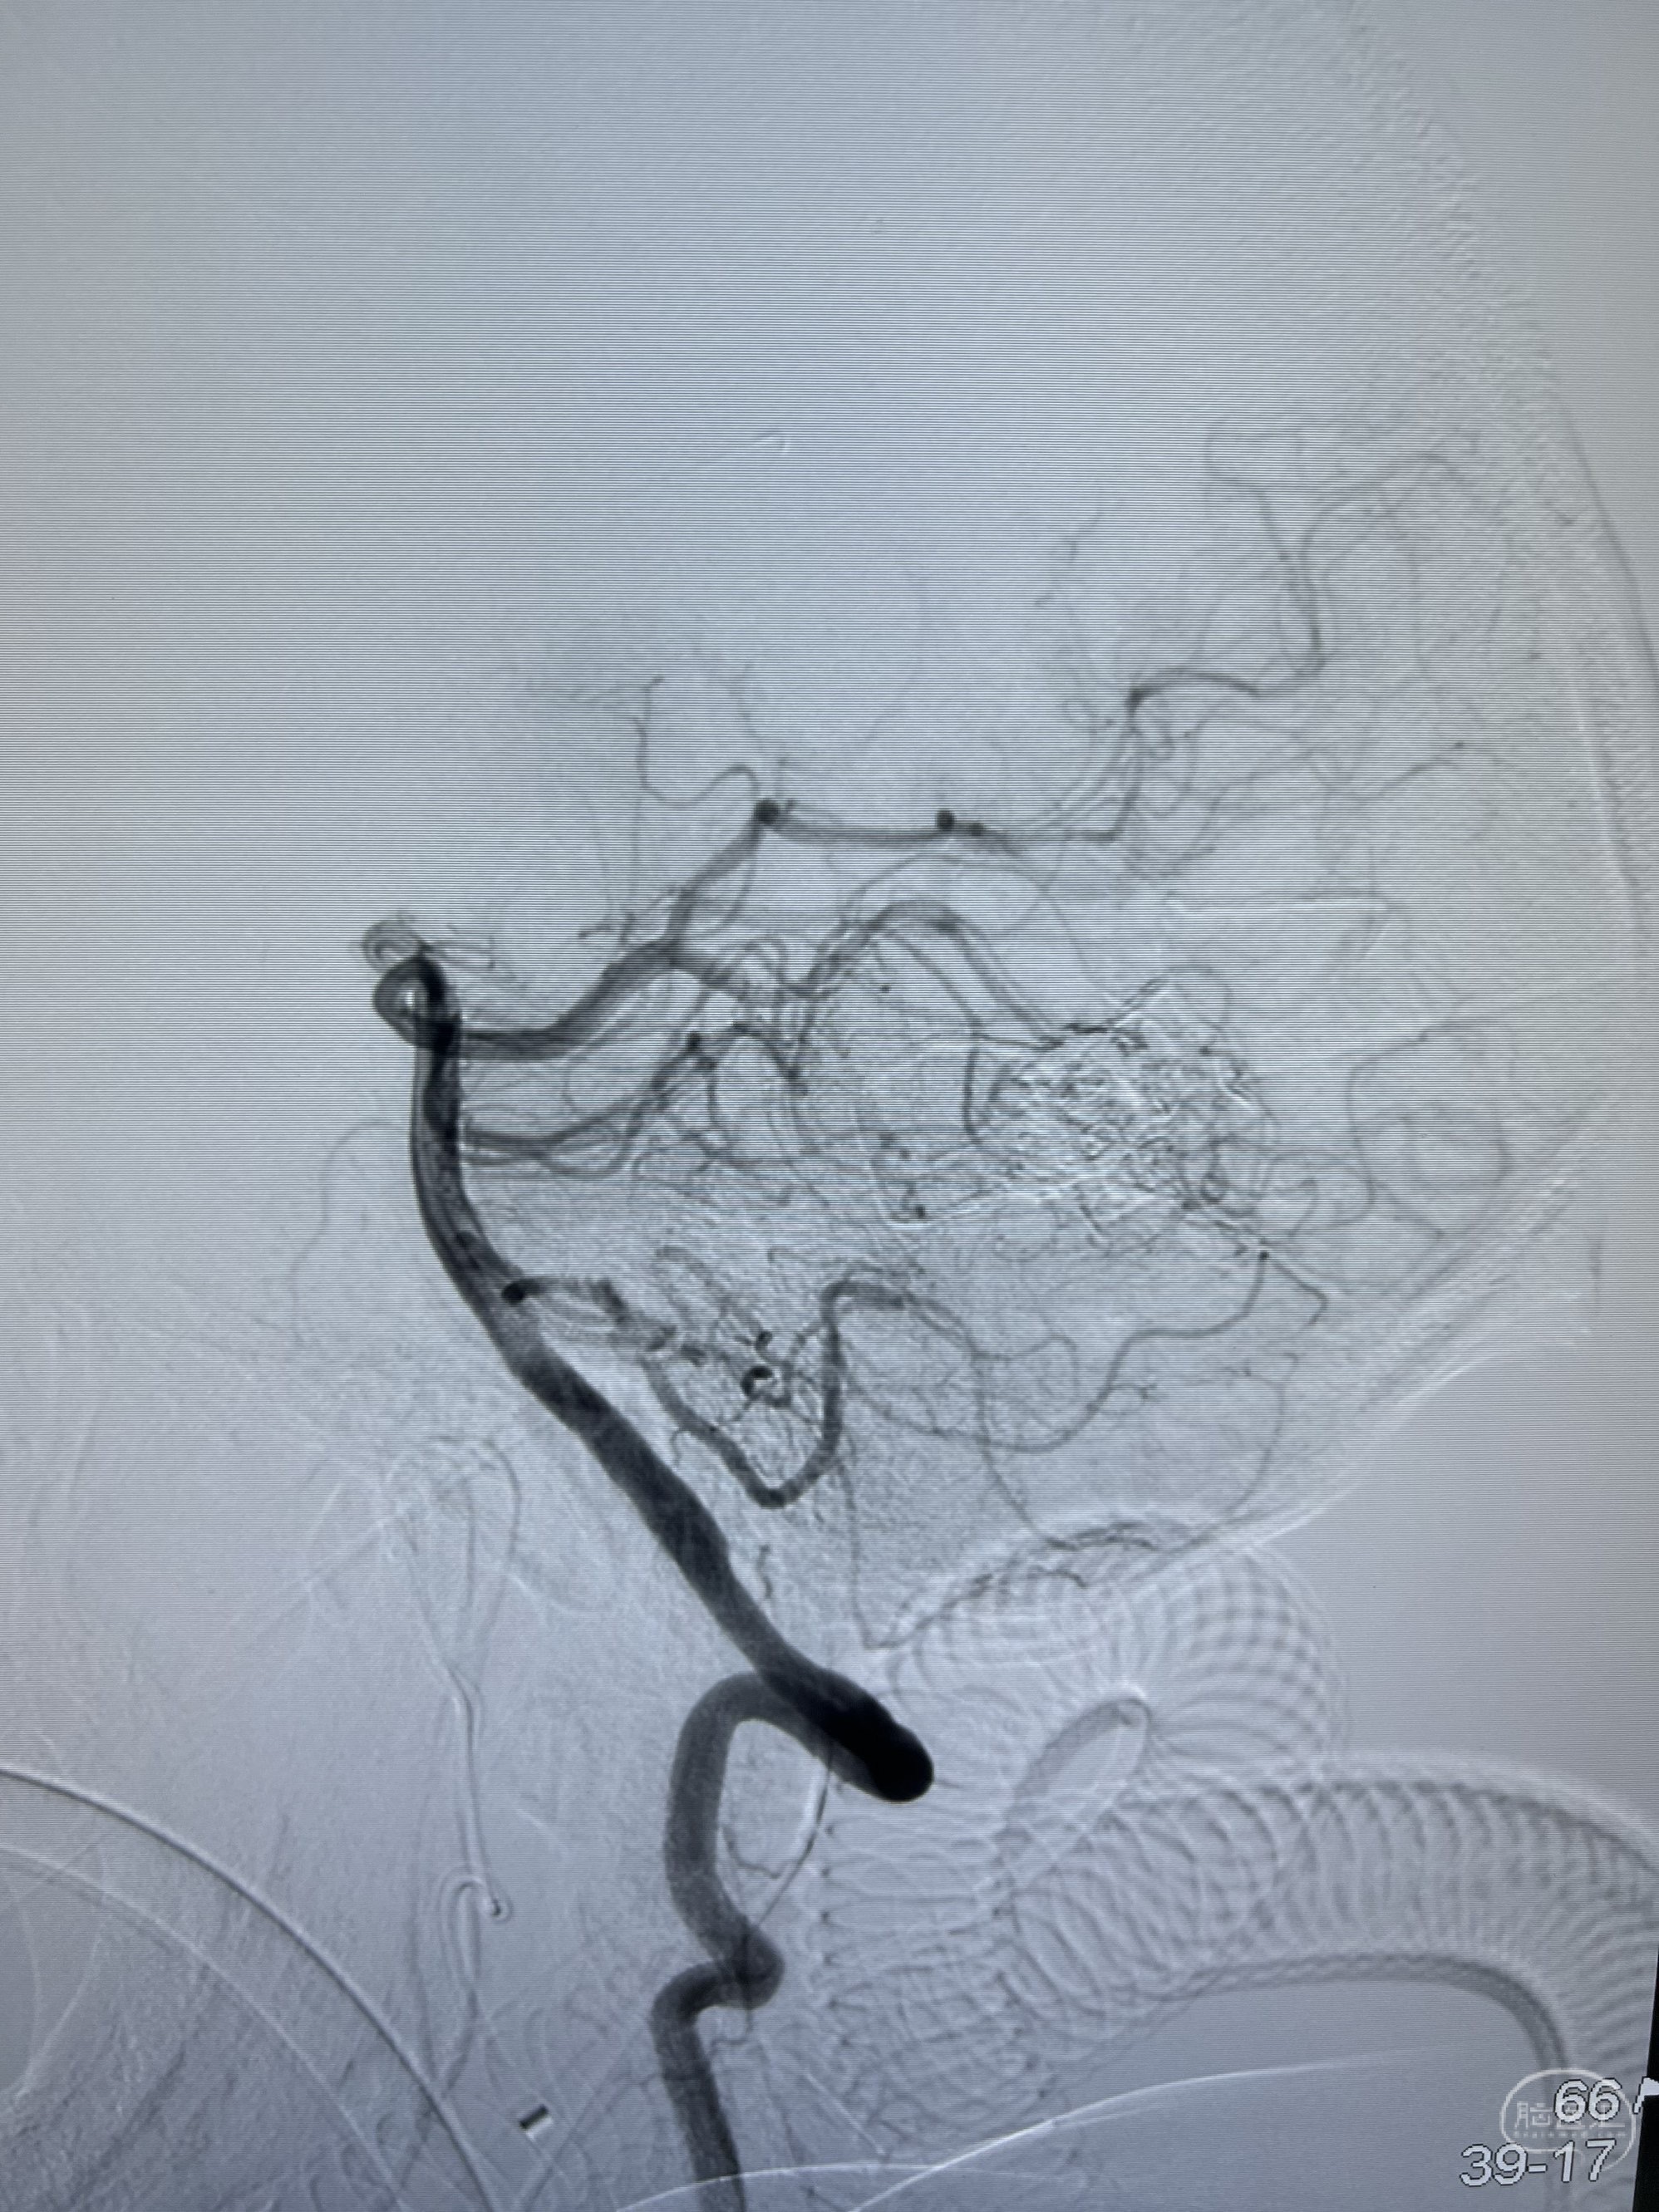

可见颈外动脉多分枝脑膜中动脉、脑膜副动脉、枕动脉、脑膜垂体干、大脑后动脉供血。

双侧股动脉置鞘,Neuromax长鞘至颈外动脉,6F115cm心玮中间导管到达上颌动脉,尽可能建立强有力的支撑。

由于此区域的DAVF常规“黄金通道”MMA比较纤细,先尝试脑膜副动脉入路,Apollo-30mm头端可解脱微导管结合0.010英寸Asahi微导丝反复尝试难以接近瘘口,微导管头端在特别弯曲位置调整时头端解脱。换用Marathon微导管难以再通过脑膜副动脉。

遂尝试Marathon微导管结合0.010英寸-200cm-Asahi微导丝经MMA途径超选至DAVF瘘口。

造影证实微导管接近瘘口及静脉端,注入onyx胶,其间从左侧股动脉鞘在右侧颈总动脉及右侧椎动脉造影,确认onyx胶已封闭瘘口及所有供血动脉。